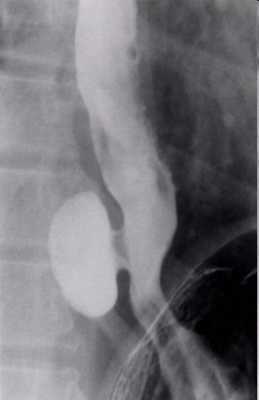

- Kontrastlı Rh-qrafiya - diaqnozu dəqiqləşdirən müayinədir.

- Rentgenoqrafik divertikul görünməsi

- Kontrastlı rentgenoqrafiya - dəqiqləşdirici müayinə üsuludur.

- Kontrastlı Rh-qrafiya - dəqiqləşdirici müayinə üsuludur.

Görüntlüləmə əlamətləri hansılardır?

Kontrast məhlulunn divertikul nahiyəsində toplanması